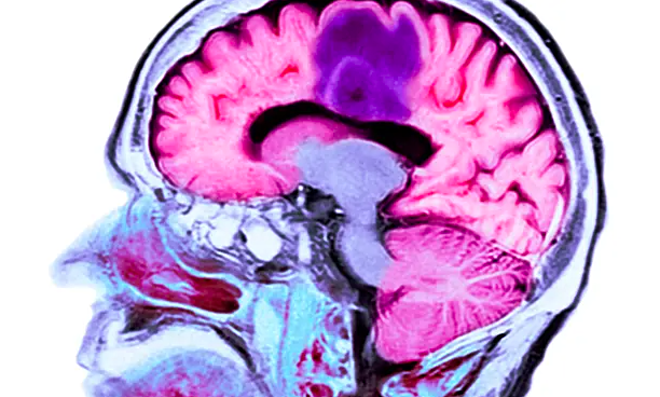

Trong nghiên cứu trên, loại vaccine có tên gọi DCVax, dành cho người mắc u nguyên bào thần kinh đệm, dạng ung thư não phổ biến và ác tính nhất. Thông thường, người bệnh chỉ sống trung bình 12 đến 18 tháng sau chẩn đoán, một số thậm chí ít hơn. Tuy nhiên, sau khi thử nghiệm vaccine, một số tình nguyện viên đã sống sót sau hơn 8 năm.